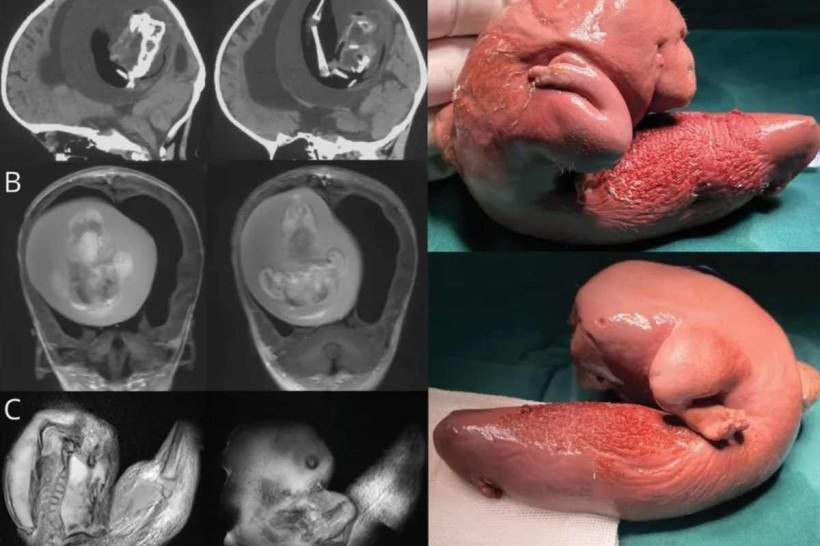

Imagens tomografia da menina chinesa

Imagens tomografia da menina chinesa (foto: Reprodução/ Zongze Li et.al)

Conforme detalhes da revista científica Neurology, a menina apresentava "atraso motor e perímetro cefálico aumentado", e por isso a remoção teve que ocorrer com urgência. Mesmo um ano após o nascimento da menina, o "gêmeo parasita" continuou a sobreviver porque compartilhou um suprimento de sangue com a irmã.

Após o remoção cirúrgica, o "gêmeo parasita" — que tinha 10cm — passou por exames e o sequenciamento de todo o genoma revelou "variantes idênticas de nucleotídeo único na criança e no feto."